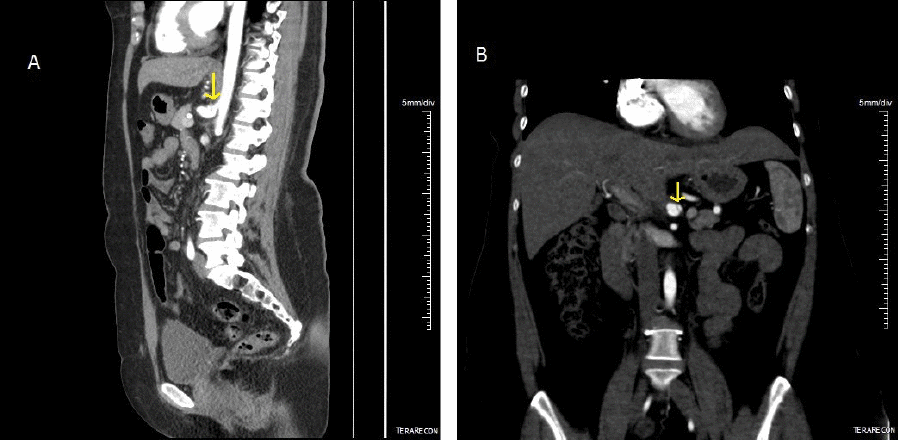

Upon presentation to our institution, the patient reported that her abdominal pain and postprandial pain had largely subsided since starting anticoagulation and making dietary changes. However, she continued to experience some epigastric fullness and discomfort. Mesenteric DUS again demonstrated dynamic elevated velocities consistent with median arcuate ligament compression. She was seen by a minimally invasive surgeon at our institution who specializes in the surgical management of median arcuate ligament syndrome. She underwent further testing per our MALS protocol, including a celiac plexus block by a pain management specialist. She endorsed the temporary resolution of her abdominal symptoms status post-celiac plexus block. Subsequently, she underwent robotic-assisted median arcuate ligament release three months later, which she tolerated well with no recurrence of her symptoms (Figure 2). CTA performed one year later showed stable dissection of the celiac artery and morphology, keeping with her history of MALS (Figure 3). There was no significant change between inspiration and expiration, and the luminal diameter of the proximal celiac artery was significantly improved overall. These findings were consistent with the release of the median arcuate ligament.

Figure 3. One Year Postoperative, Sagittal, and Coronal CTA. Published with Permission

A) Improved compression of celiac artery and worsening post stenotic dilation (arrow); B) stable celiac dissection (arrow).